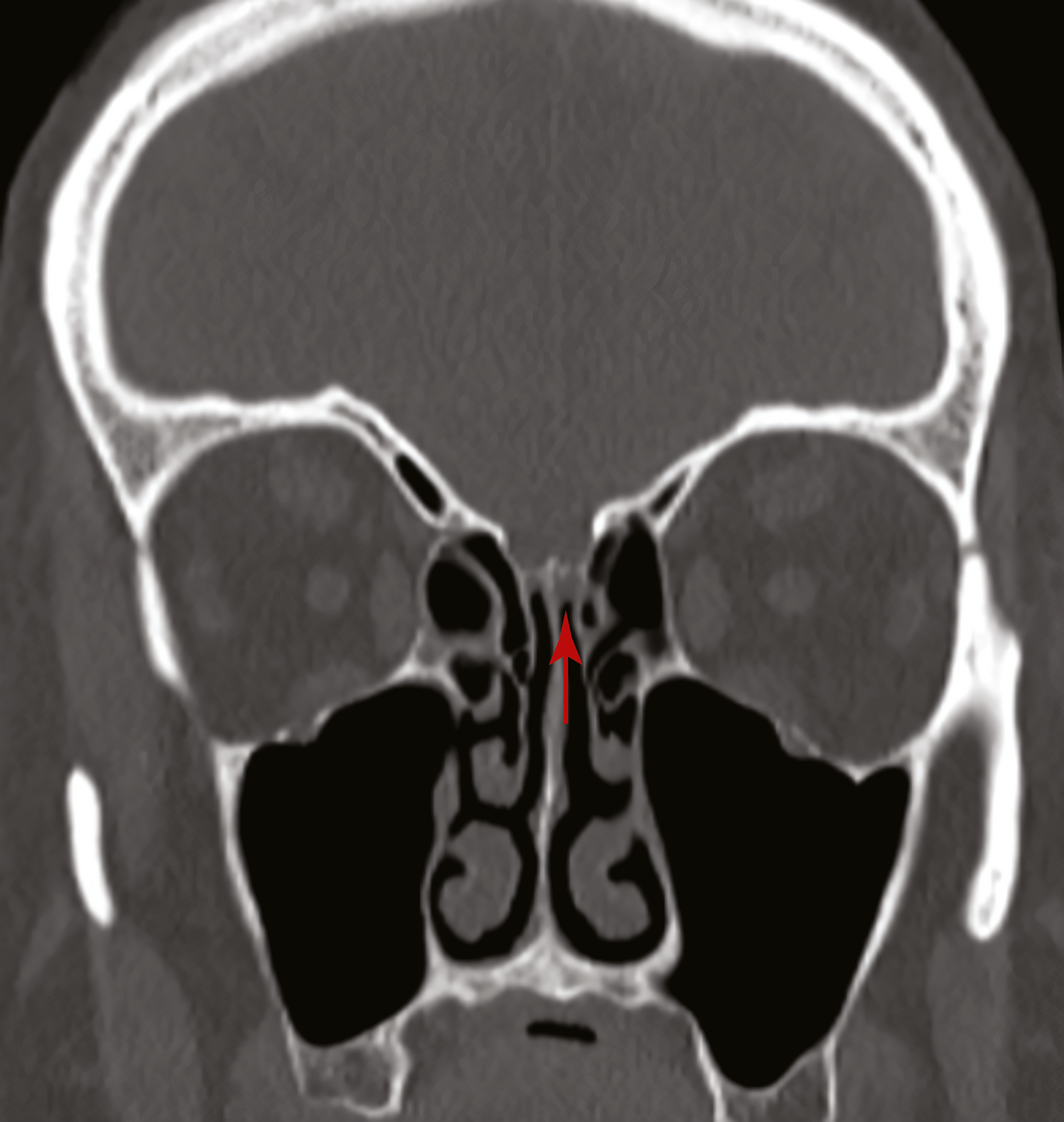

Box 1 – Coronal view of a computed tomography scan of the sinuses showing a defect in the left cribiform plate before the insertion of a fat plug (arrow)

A 67‐year‐old woman was referred to our ear, nose and throat department with confirmed cerebrospinal fluid (CSF) rhinorrhoea. She was recently treated for proven bacterial meningitis, having presented to a regional hospital with headache, nausea and photophobia 2 months previously. The patient precisely recalled the onset of unilateral clear rhinorrhoea, which occurred within hours of an “extremely painful” coronavirus disease 2019 (COVID‐19) swab test. This occurred approximately 48 hours prior to presentation to the emergency department. She had no other historical or medical risk factors for a CSF fistula (eg, previous surgery, trauma) nor harboured any stigmata of idiopathic intracranial hypertension. Intra‐operative evaluation confirmed a small, well demarcated defect (2–3 mm) in the left anterior skull base in the posterior cribriform plate (Box 1 and Box 2). The defect was successfully repaired with a fat plug and free mucosa overlay graft. She made a full recovery and remains leak‐free. Given the historical description, time frame and clinical findings, we believe the injury to be a complication of the COVID‐19 swab.